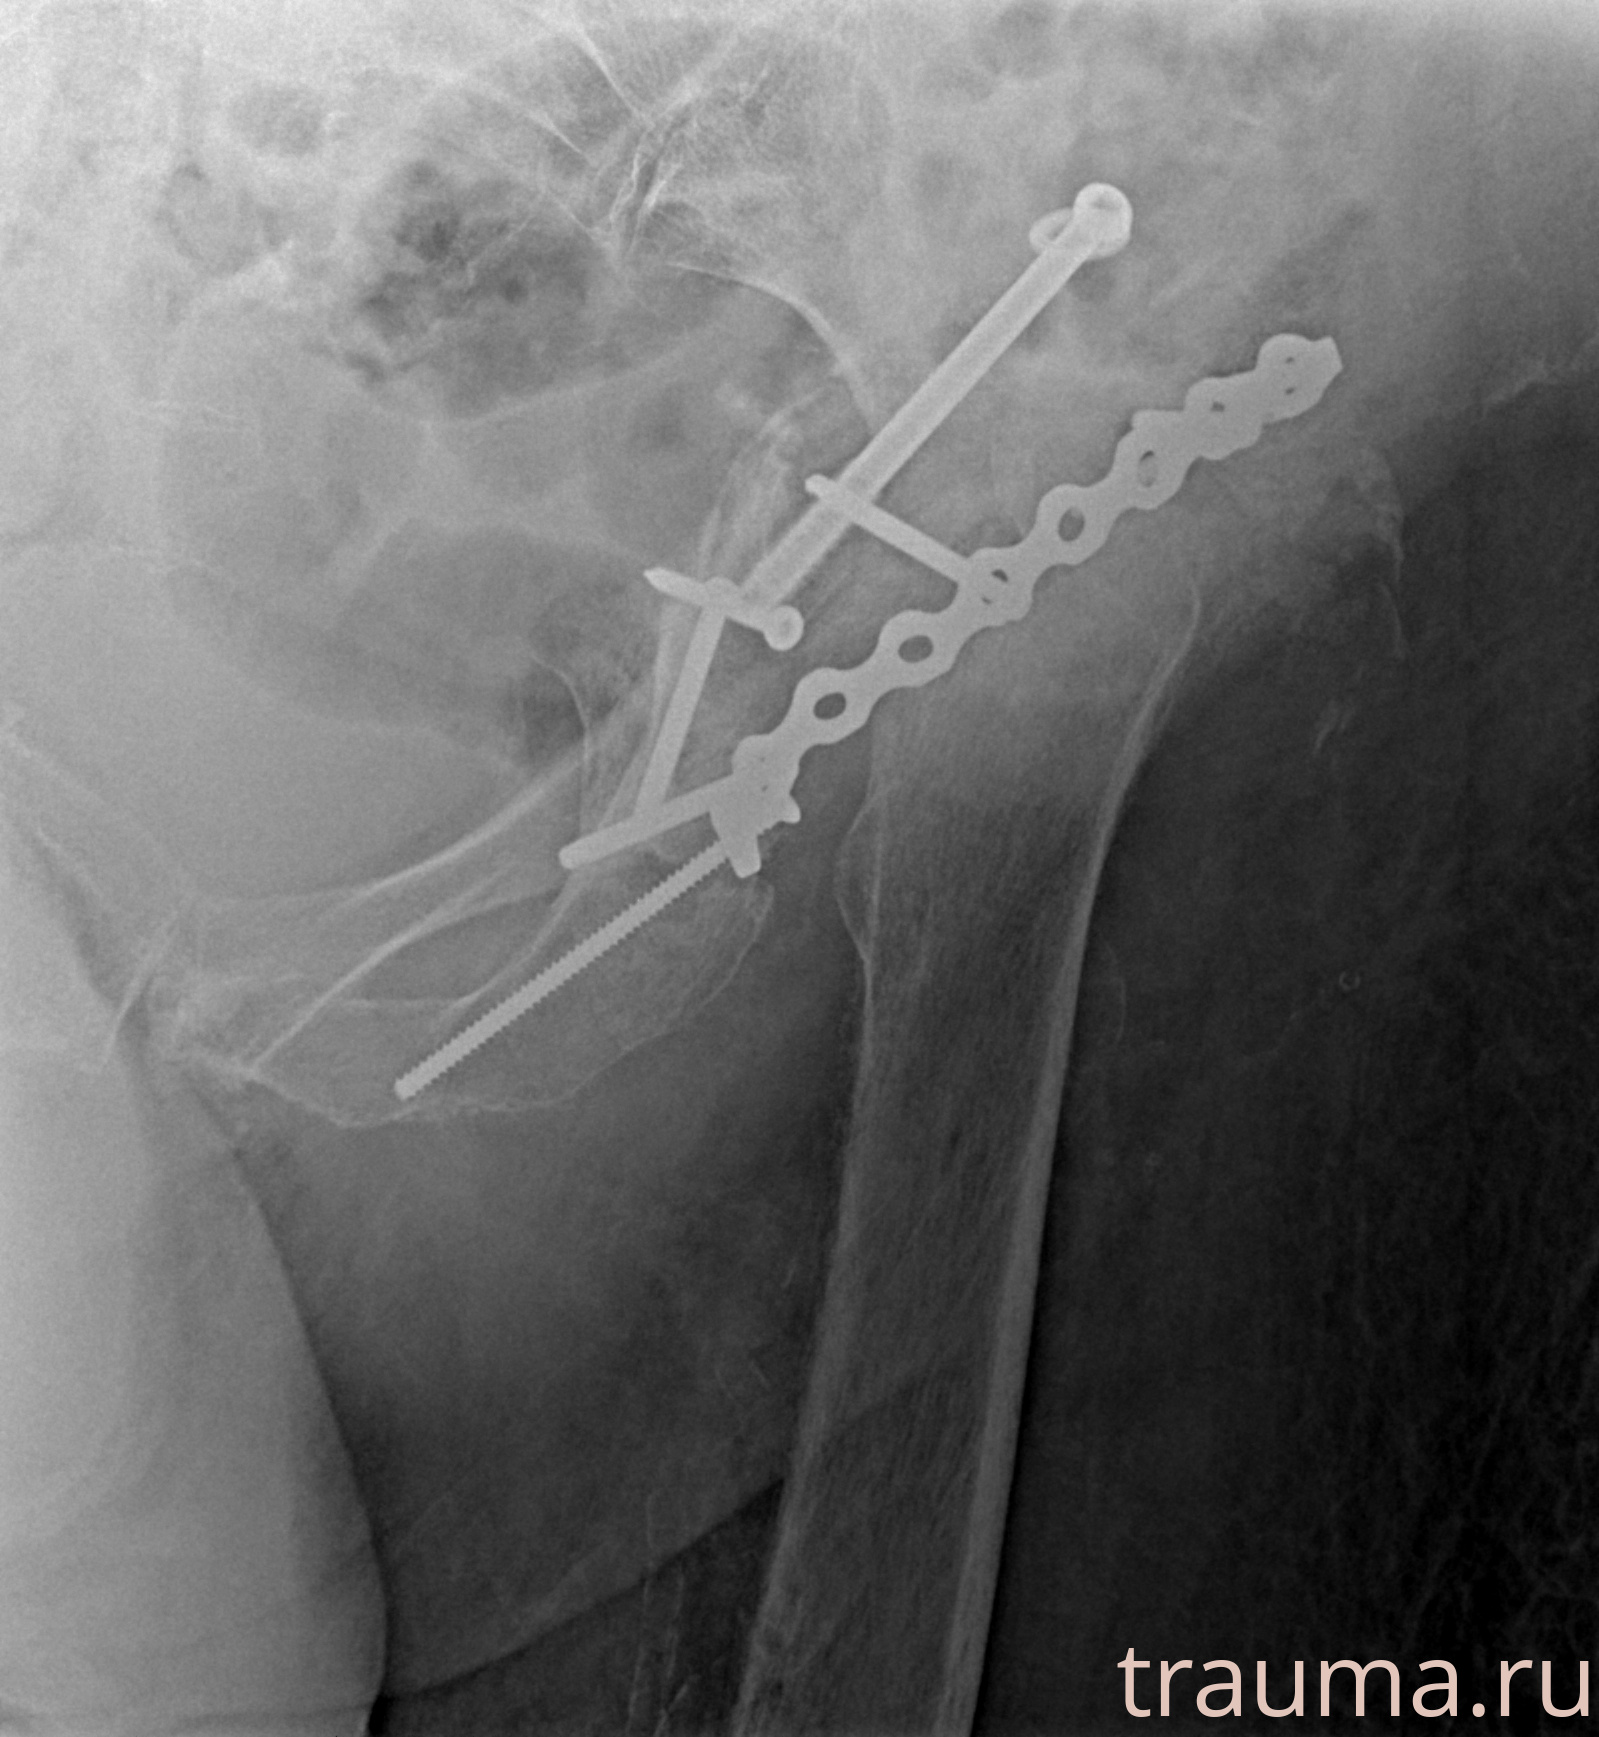

Рентгенограммы

Рентген на дому: по вашему адресу приезжает врач-рентгенолог, травматолог-ортопед с мобильным рентгеновским аппаратом, проводит диагностику травмы или заболевания, делает необходимые рентгенограммы, дает рекомендации по дальнейшему лечению. Получить качественные снимки в домашних условиях возможно благодаря уникальной методике, разработанной МосРентген Центром для института  Склифосовского